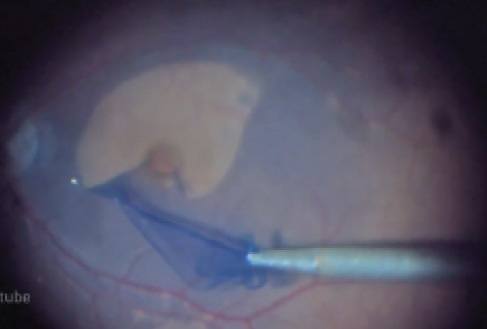

María H. Berrocal, MD, presents a case of a 76-year-old male who had undergone surgery for a traumatic giant retinal tear, cataracts, dislocated lens, and hyphema. He detached again under oil 2 months later.

Giant retinal tears are uncommon, and most surgeons hope they encounter only a handful of such cases each year. Use of perfluorocarbon liquid tamponade and small-gauge vitrectomy generally yields positive results. Still, given the large number of retinal pigment epithelial cells exposed in the presence of a giant retinal tear, proliferative vitreoretinopathy (PVR) more commonly occurs. It should be unsurprising, then, that the cause of redetachment in Dr. Berrocal’s case is subretinal PVR.

The patient in this case had an extensive 12-clock hour giant tear, providing the surgeon access to the subretinal space. Eyes in which smaller tears are present may require a focal retinotomy to allow removal of subretinal membranes. I often start with Maxgrip forceps (Alcon) rather than Eckhardt forceps; the former provide superior engagement of subretinal membranes.

Dr. Berrocal used her light pipe as a second instrument to provide countertraction, obviating the need for a bimanual technique with a chandelier or a second lighted instrument.

As Dr. Berrocal’s Eyetube video demonstrates, the cutter alone can serve as a useful multifunctional tool during subretinal membrane removal. Using it in this way is both cost-effective and efficient. Small-gauge cutters have seen increased use in cases of complex diabetic vitrectomy. Will they become similarly popular for PVR membranectomy?